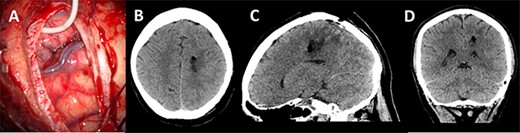

(A) Axial T1-weighted image with gadolinium showing the lesion with imposed DTI tractography of the CST; (B) planned trajectory for insertion of the tubular retractor guided by the preoperative integrated anatomical and functional motor mapping.

5-Aminolevulinic Acid (5-ALA) was given orally 2 h before the surgery. The least disruptive trajectory was selected taking into account the previous biopsy and the preoperative mapping information (Fig. 3). Under Stealth guidance, a skin incision was made overlying the planned craniotomy site. After the craniotomy, the dura was opened and a subdural strip of electrodes was placed over the primary motor cortex. Replicable motor responses from the hand muscles were obtained at 7 mA current intensity (Fig. 4). Motor evoked potentials (MEPs) were obtained continuously throughout the procedure. A transsulcal parafascicular approach was used. The sulcus was opened sharply under the microscope. At the depth of the sulcus, a preselected tubular retractor (NICO BrainPath 75 mm × 13 mm) was passed to the superficial surface of the lesion. While performing brain cannulation to the lesion, a monopolar probe (INOMED©) navigated with SureTrack (MEDTRONIC©) was used to perform continuous subcortical stimulation, train-of-five technique using high-frequency stimulation.

Two independent techniques were used to dissect the ipsilateral CST with StealthViz Software (MEDTRONIC©): region of interest (ROI) technique and TMS-seeded technique. In the first one, two ROIs were defined, precentral gyrus and midbrain at the level of the superior cerebellar peduncle, the anatomical streamlines going through both regions were selected. In the second technique, the positive nTMS responses for the upper and lower limb were selected independently as ROIs and the other ROI was in midbrain at the level of the superior cerebellar peduncle. Both dissections of the CST were used as they provided an anatomical and functional assessment of the tract. The tumour was delineated in the Cranial Software (MEDTRONIC©) and the preoperative cortical and subcortical mapping was integrated in a 3D model (Fig. 2).